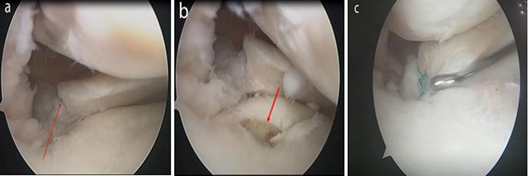

All the patients underwent posterior medial meniscus root repair by transtibial tunnel pull-out technique. To confirm the diagnosis, a diagnostic arthroscopy is performed and a tibia socket is created for easy passage of drill guide. Through the anteromedial portal, drill guide is inserted and a guide tip is placed at the footprint of meniscus root. Medial to the tibial tuberosity a skin incision of 2-4cm is made and the outer cannula is impacted into the anterior cortex of the tibia. Through the inner cannula a guide wire of 2.4-mm is drill till it reach the tip of the guide intra-articularly. A 3.5-mm Arthrex FlipCutter with 8 mm diameter head is drilled through the same tunnel of the 2.4- mm wire. The FlipCutter head is deployed inside the joint and the tibia is retro drilled up to a depth of 5-mm to create socket for fixation of meniscus root. A number 0-Fiberwire (Arthrex) suture loop is passed in the posterior medial meniscus root with a self-retrieving suture passing device (Firstpass mini, Smith& Nephew). To create a cinch configuration the Fiberwire suture is passed through the loop and tightened around the posterior medial meniscus root. A second number 0 -Fiberwire (Arthrex) is similarly used to create a second repair point in the root. All the sutures are shuttled down through the tibial tunnel to exit at anteromedial tibial surface. To fixed the repair meniscus root into the tibial socket a moderate tension is applied.. With knee in 30° of flexion both the sutures are tied over suture post fixed on anteromedial tibial surface 1cm distal to tibial tunnel. Using a probe, the stability of fixation is confirmed (Figure 1).

Figure 1 Arthroscopic images of a left knee.

a) Medial meniscus posterior root tear (red arrow). b) Tibial socket for root fixation (red arrow). c) Medial meniscus posterior root after repair.